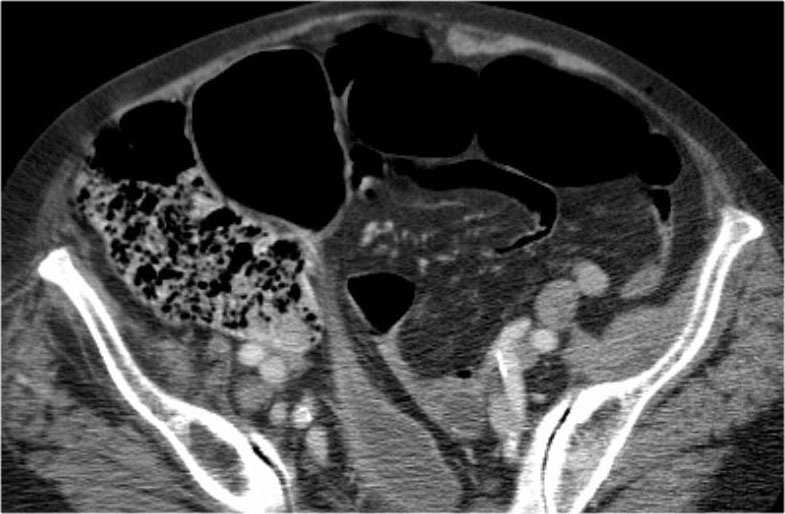

Đây là một bệnh nhân bị tắc ruột non.

Cuộn qua các hình ảnh.

Bạn có thể tìm thấy quai kín và nguyên nhân gây ra nó không?

Hình ảnh CT của tắc ruột non dạng quai kín phụ thuộc vào hai yếu tố:

- chiều dài đoạn ruột tạo thành quai kín

- hướng của quai ruột so với mặt phẳng tạo ảnh

Nếu quai kín ngắn và nằm trong mặt phẳng tạo ảnh, chúng ta sẽ thấy quai ruột hình chữ U hoặc chữ C.

Một hình ảnh quan trọng khác của tắc ruột dạng quai kín là các quai ruột non giãn xếp theo hình nan hoa với các mạch máu mạc treo hội tụ về một điểm trung tâm.

Hình ảnh này hầu như luôn do xoắn ruột non gây ra.

Nếu quai kín dài hơn và định hướng vuông góc với mặt phẳng cắt, chúng ta sẽ thấy một cụm quai ruột như trong ca lâm sàng bên trái.

Đôi khi điều này khó nhận biết chỉ trên các lát cắt ngang và các tái tạo mặt phẳng coronal hoặc sagittal có thể hữu ích.

Trong ca này, cũng có phù nề mạc treo và cổ